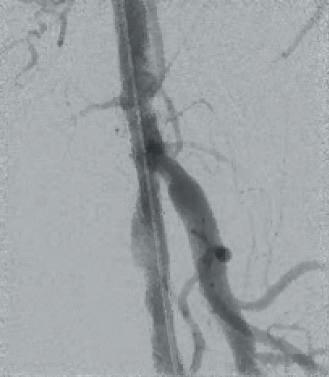

DCB PTA catheter, BD Bard) which was inflated for three minutes at 8atm. Subsequent angiography showed a very good lumen gain without significant restenosis within the target lesion (Figures 3 and 4). We finalized the intervention with full recanalisation of the SFA using three more DCBs and one bailout stent implantation using the new triaxial, 4F Pulsar-18 T3 nitinol self-expanding stent system (6x150mm; Biotronik). After implantation of the Pulsar-18 T3 stent and a 6mm balloon post dilatation, a brisk flow was seen within the whole length of the target vessel and a straight flow into the foot via the patent posterior tibial artery. Follow-up examination of the patient the next day showed an ABI of 0.9 on the left side.

Figure 3

Figure 4